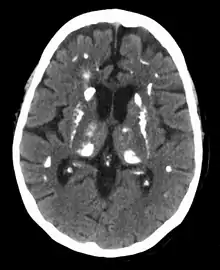

Hyperparathyroidism can cause hyperchloremia and increase renal bicarbonate loss, which may result in a normal anion gap metabolic acidosis.[7] ALP level can be elevated due to bone turnover. Additionally further tests can be completed to rule out other causes and complications of hyperparathyroidism including a 24-hour urinary calcium for familial hypocalciuric hypercalcemia, DEXA scan to evaluate for osteoporosis, osteopenia, or fragility fractures, and genetic testing.[36][37][38][39] Additionally a CT scan without contrast or renal ultrasound can be done to assess for nephrolithiasis and/or nephrocalcinosis if there is concern for it.[39]